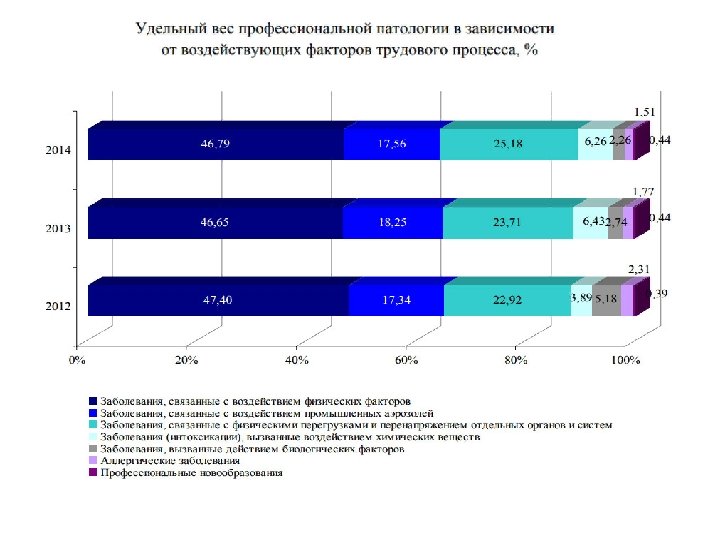

Структура профзаболеваемости в РФ, 2016 В структуру профессиональной заболеваемости по этиологическим факторам входили: заболевания, связанные с воздействием физических факторов 42, 6%; заболевания, вызванные воздействием промышленных аэрозолей 22, 3%; заболевания, связанные с физическим перегрузками и перенапряжением отдельных органов и систем, 19, 3%; заболевания (интоксикации), вызванные воздействием химических факторов, 8, 0%; заболевания, вызванные действием биологических факторов, 4, 5%; аллергические заболевания 2, 9; профессиональные новообразования 0, 4%

Структура профзаболеваемости в РФ, 2016 В структуру профессиональной заболеваемости по этиологическим факторам входили: заболевания, связанные с воздействием физических факторов 42, 6%; заболевания, вызванные воздействием промышленных аэрозолей 22, 3%; заболевания, связанные с физическим перегрузками и перенапряжением отдельных органов и систем, 19, 3%; заболевания (интоксикации), вызванные воздействием химических факторов, 8, 0%; заболевания, вызванные действием биологических факторов, 4, 5%; аллергические заболевания 2, 9; профессиональные новообразования 0, 4%